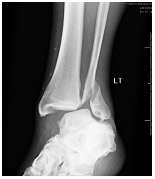

Diploma Orthopedics, Fellowship in Foot & Ankle Surgery from Vadodara, Chennai, Spain, U.K.

1st and only exclusive foot & Ankle surgeon of Saurashtra-Kutch region. Practicing orthopedics since 2014 with dedicated practice of ankle and foot surgeon since 2021